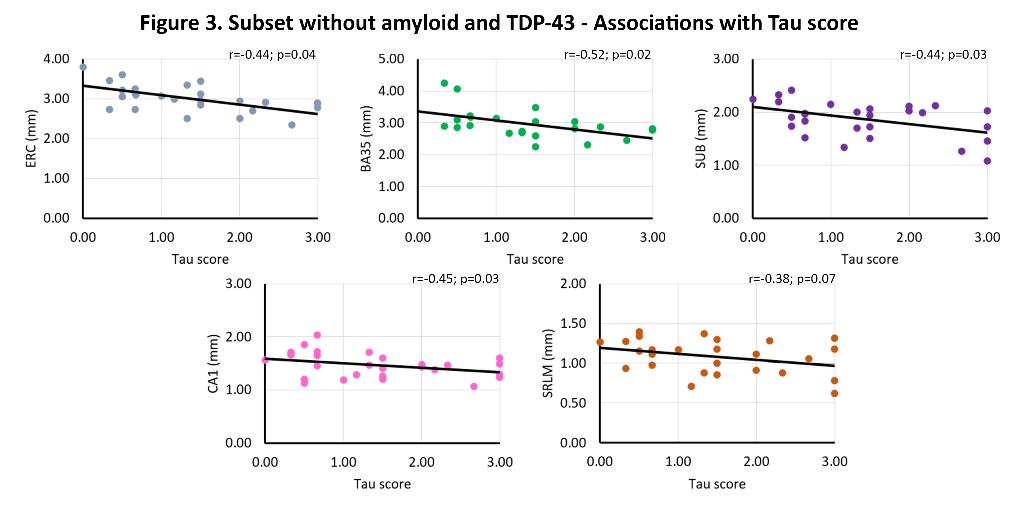

Tau, TDP-43, β-amyloid and α-synuclein pathology were rated (0-absent – 3-frequent) in the hippocampus and entorhinal cortex (ERC) of 58 individuals with and without neurodegenerative diseases (mean age 74.7 years, 39.7% female). Thickness measurements using a semi-automated approach were obtained from 0.2x0.2x0.2 mm3 post-mortem MRI scans of excised MTL specimens from the contralateral hemisphere in the ERC, Brodmann Area (BA) 35 and 36, parahippocampal cortex (PHC), subiculum (SUB), cornu ammonis (CA)1 and the stratum radiatum lacunosum moleculare (SRLM). Spearman’s rank correlations were performed, correcting for age, sex and hemisphere, including all four proteinopathies in the model.

We find significant associations of 1) TDP-43 with all subregions (r=-0.27 – r=-0.46, trend for subiculum), and 2) tau with ERC (r=-0. 26, trend), BA35 (r=-0.31) and SRLM (r=-0.33). In β-amyloid and TDP-43 negative cases, we find strong significant associations of tau with ERC (r=-0.40, trend), BA35 (r=-0.55), subiculum (r=-0.42), CA1 (r=-0.47) and SRLM (r=-0.38, trend). See figures 1-3.

This unique dataset showed widespread atrophy in relation to TDP-43 pathology and atrophy in early Braak regions and tau pathology. Moreover, the strong association of tau with thickness in early Braak regions in the absence of β-amyloid and TDP-43 is indicative for a role of Primary Age Related Tauopathy in neurodegeneration.